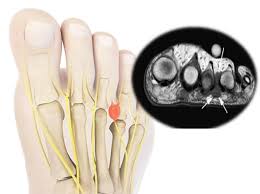

발목터널증후군

발목터널증후군은 발목을 지나는 신경이 손상을 입어 발 전체에 찌릿찌릿한 통증을 유발하는 질환입니다. 특히 40세 이상의 여성에서 발병률이 높습니다.